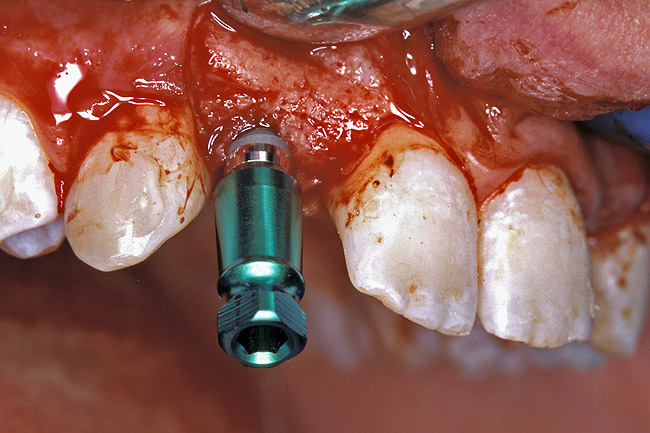

Before the day of surgery, the patient was seen by the orthodontist for the removal of the orthodontic brackets. The patient still was not pleased with the position of the two centrals, and it was determined that this would be addressed after implant placement (Figure 13A). The anatomical variations of the crestal tissue and lack of interdental papilla can be appreciated in the close-up views of the right and left sites (Figure 13B and 13C). There were no surprises on the day of surgery as all of the decisions were made during the planning phase, before the scalpel ever touched the patient. The occlusal view of the CT 3D model revealed the wider alveolar ridge on the right side and thinner crest on the left side (Figure 14A). This was confirmed when the full thickness mucoperiosteal flaps were elevated, and the underyling bone revealed (Figure 14B). The tooth-borne templates were designed to facilitate the drills and drilling sequence specific to the diameters of the predetermined implants (Figure 15A). Each template contained an embedded 5-mm long stainless steel tube, which was approximately 0.2-mm wider than each drill (just wide enough to allow for the drills to rotate freely). Once positioned over the natural teeth, the template was secure and offered precision accuracy in transferring the implant locations from the original software-designed plan, allowing the potential for internal and external irrigation (Figure 15B). The 3.7-mm diameter Tapered Screw-Vent implant drilling sequence requires three drills: pilot, intermediate, and final sizing. Thus, three separate templates were fabricated to a.commodate these sizes. The templates were removed easily and replaced with the next sequential size in less time than it takes to change the drill on the surgical handpiece. After the osteotomies had been.completed, the implants were delivered to the site (Figure 16A and Figure 16B). For this internal hex connection implant, the author r.commends that the flat of the antirotational hex be positioned to the facial for proper orientation of the restorative.components (Figure 17A). Preprepared margins were created from a milled titanium fixture mount transfer post, which was delivered to the implant as support for an immediate transitional restoration. The facial “dot” helped confirm the orientation of the abutment to the facially positioned flat side of the internal hex connection (Figure 17B). Before cementation of the transitional acrylic restorations, a closed-tray, fixture-level impression was made, and a soft-tissue model fabricated.

Figure 16a  After (A) the osteotomies were completed, (B) the implants were placed.

Figure 16a

Figure 16b  After (A) the osteotomies were completed, (B) the implants were placed.

Figure 16b